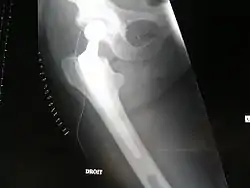

Fracture de l'extrémité supérieure du fémur

Une fracture de l'extrémité supérieure du fémur (ou fracture de l'extrémité proximale du fémur), appelée couramment « fracture de la hanche » ou fracture du col du fémur, désigne une fracture du fémur localisée au niveau de son épiphyse supérieure.

Diagnostic

Le diagnostic est posé après une chute avec le plus souvent impossibilité de se relever. La jambe fracturée est raccourcie, le pied est tourné vers l'extérieur. Parfois, la fracture est engrenée et le patient peut continuer à marcher pendant plusieurs jours.

Le diagnostic est confirmé par des radiographies de la hanche de face et de profil.

Il existe plusieurs classifications des fractures selon la localisation et selon le déplacement.

Elles se repèrent par la classique triple déformation du membre inférieur qui est en adduction, raccourcie et en rotation externe et on la confirme par un bilan radiographique (bassin et hanche) où l’on peut distinguer :

- deux types via la classification de Pauwels selon l’orientation du trait fracturaire : vertical instable et horizontal stable.

- quatre stades via la classification de Garden selon l’orientation des travées qui bougent avec le déplacement de la tête fémorale : si elles se déplacent vers le haut on parle de valgus (1), ouvrant l’angle cervico diaphysaire ; alors que vers le bas, fermant l’angle cervico diaphysaire on parle de varus (3-4).

Le risque de nécrose augmente avec le déplacement et donc avec le stade de Garden.